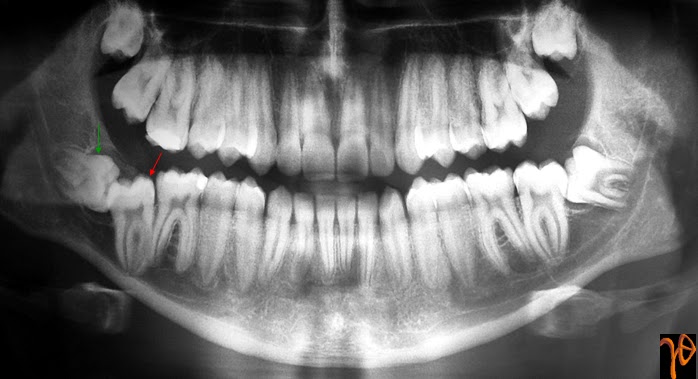

Μια περίπτωση εγκλείστου κάτω δεύτερου μόνιμου γομφίου

Η συχνότητα εγκλείστων κάτω δεύτερων μονίμων γομφίων είναι εξαιρετικά σπάνια και κυμαίνεται από 0,6-3/1000. Παρουσιάζουμε μια τέτοια περίπτωση σε άνδρα 18 χρονών με φυσιολογική σύγκλειση και χωρίς οδοντικές ή οδοντογναθικές ανωμαλίες. Ο έγκλειστος δεύτερος γομφίος εμφάνιζε κάθετη κλίση σε σχέση με τον πρώτο γομφίο (Vedtofte H. κ.σ., 1999) και συνοδευόταν από την παρουσία εγκλείστου τρίτου γομφίου και την ανάπτυξη μικρού μεγέθους οδοντοφόρας κύστης (Εικ. 1).

Εικόνα 1. Πανοραμική ακτινογραφία στην οποία αποκαλύπτονται οι έγκλειστοι #47 (κόκκινο βέλος) και #48 (πράσινο βέλος).

Παρά την πιθανή συσχέτιση διαφόρων παραγόντων, η αιτιολογία της έγκλεισης και μη ανατολής των κάτω δεύτερων μονίμων γομφίων παραμένει αδιευκρίνιστη. Επιπλέον λόγω του περιορισμένου...